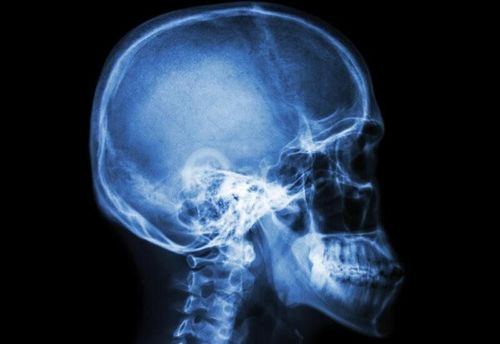

Chủ đề Chụp X - quang sọ não